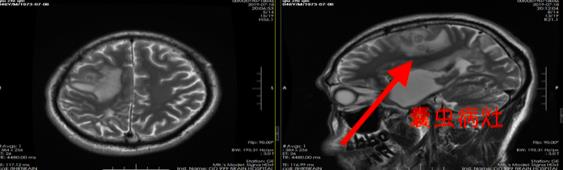

患者陆某及家属回忆,陆某出现发作性抽搐、流口水和口角歪斜的症状已经有3年了。“他一发作起来就不省人事,无论怎么叫都没有反应,而且每次发作都会持续十几分钟,不过清醒之后就想不起发作的情形了。”陆某的家属说。在这期间偶尔也有吃药,但没有明显的效果,直到上周再次大发作,为寻求进一步诊治,陆某来到了广东三九脑科医院。该院神经外三科副主任杨宝应接诊后,通过影像和视频脑电图检查,发现陆某颅内右侧额叶有囊性占位和癫痫样放电,考虑寄生虫感染的可能性较大。

术前